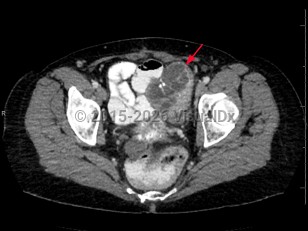

Diverticular disease

Rectal carcinomaRectal carcinoma

Psoas abscess